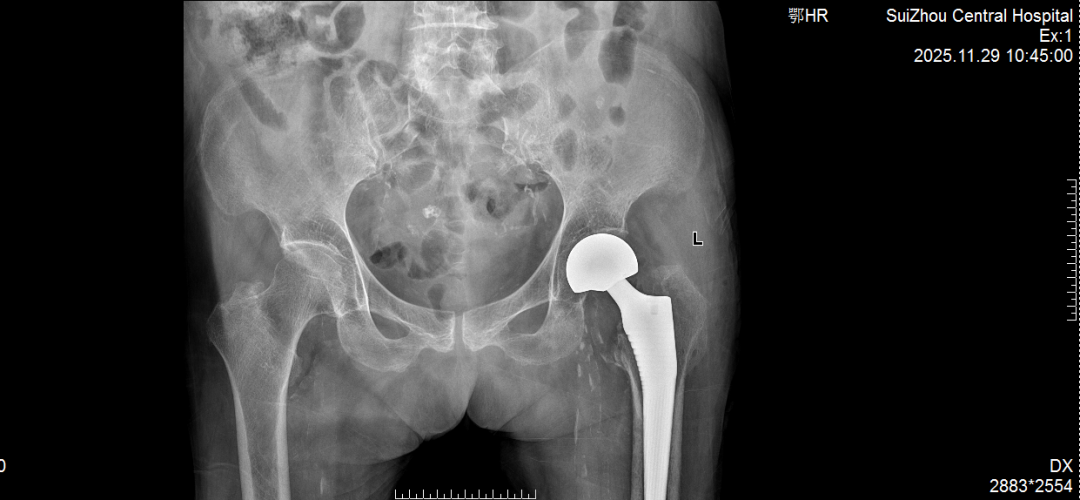

在充分的术前准备与精细的术中操作下,团队成功为患者实施人工髋关节置换术。手术时间短、出血少,极大减轻了患者身体负担。术后,在护理团队的精心照护与康复指导下,老人恢复良好,疼痛显著缓解,生活质量大幅提升。看着老伴重露笑容,老先生感激满怀。

术前术后